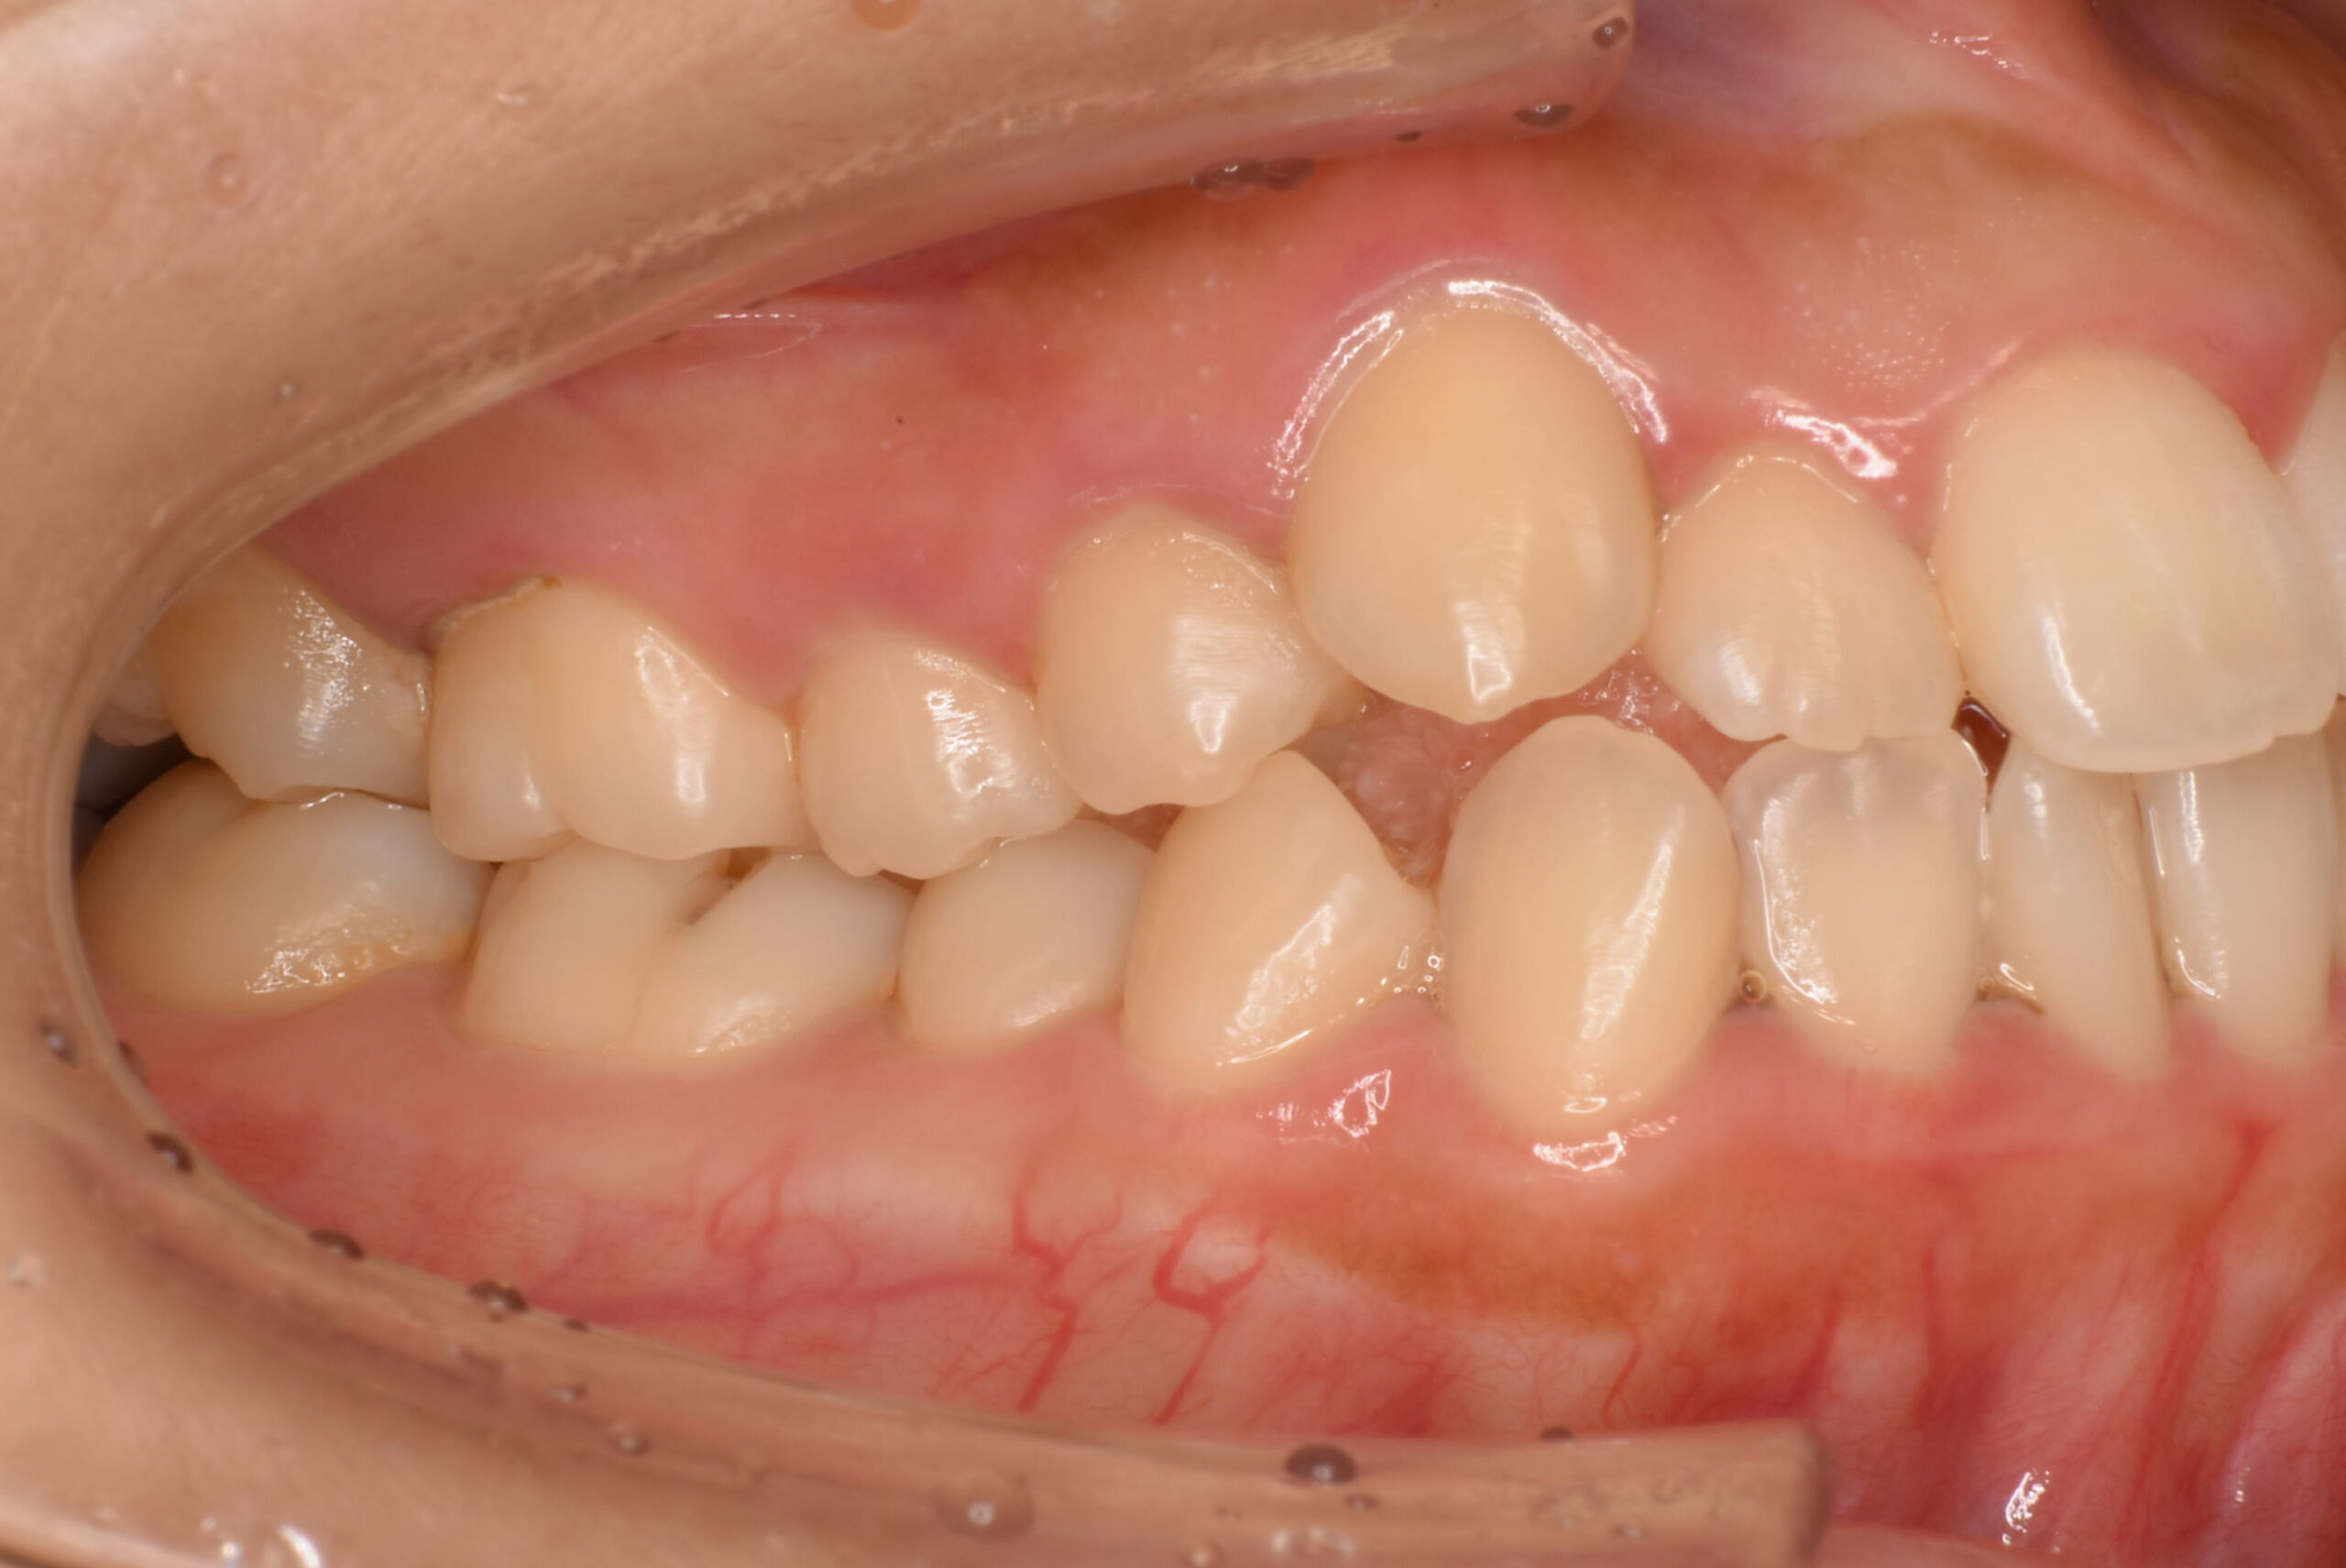

治療前_右側方

| 治療内容 | 患者様は、歯のガタつきやデコボコした不揃いな歯並び、歯に汚れがつきやすく磨きにくいことを主訴に来院されました。10年以上ぶりの歯科受診で、歯ぐきからの出血(歯肉炎:歯肉病の初期症状)が多く見られたため、インビザライン治療に入る前にブラッシング指導(TBI)や歯周病治療を行い、口腔内環境を整えてから矯正治療を開始しました。 治療開始前には左上の歯の虫歯治療を行い、その後インビザライン治療をスタートしました。抜歯は行わず、非抜歯矯正で歯列を整える方針とし、歯の移動に必要なスペースを確保するために IPR を行いながら治療を進めました。インビザライン治療と並行して歯周病治療も継続し、歯列の改善と口腔内の健康維持の両方を図りました。 |